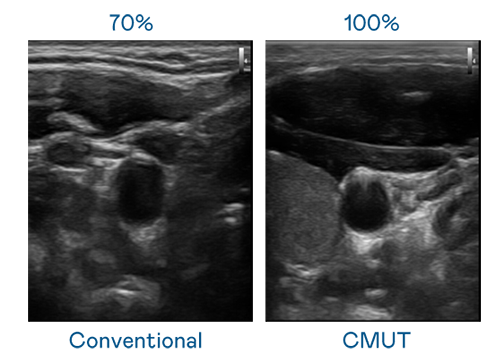

CMUT ¼¼ÊõÊÇÒ»ÖÖÓõçÈÝʽ΢»úµçÔª¼þÀ´·¢Éú³¬Òô²¨Ñ¶ºÅµÄ¼¼Êõ¡£Ó봫ͳ PZT ѹµçʽ¼¼ÊõÏà±È£¬CMUT Ƶ¿íÔö¼Ó 30%£¬¸ü¿íƵµÄ³¬Òô²¨Ñ¶ºÅÈÃÓ°Ïñ½âÎö¶È´ó·ùÌáÉý£¬ÊÇʵÏÖ¸ßÓ°ÏñÆ·ÖÊÒ½ÁƳ¬Òô²¨É¨Ãè¡¢´Ù½ø¾«×¼Ò½ÁÆÉú³¤µÄÒªº¦¼¼Êõ¡£

³¬Òô²¨Ó°ÏñµÄ½âÎö¶ÈÆéá«£¬Ê×ÏÈÈ¡¾öÓÚ̽ͷÄÜ·¢³öµÄѶºÅƵ¿í¡£ÌÚÁúÍÅÌåÖйú CMUT ¿ÉÌṩ¸ßÇåÎúµÄ³¬Òô²¨Ñ¶ºÅ£¬Ìṩ¸ßƵ¿í¡¢¸ßÁéÃô¶È¡¢Ó°ÏñÎÆÀíϸ½Ú¸ü¸ßµÄ³¬Òô²¨Ó°Ïñ£¬ÐÖúÒ½»¤ÈËÔ±Ëõ¶ÌÓ°ÏñÅжÁʱ¼ä¼°ÀûÓþ«×¼µÄÒ½ÁÆÓ°Ïñ½øÐÐÕï¶Ï¡£